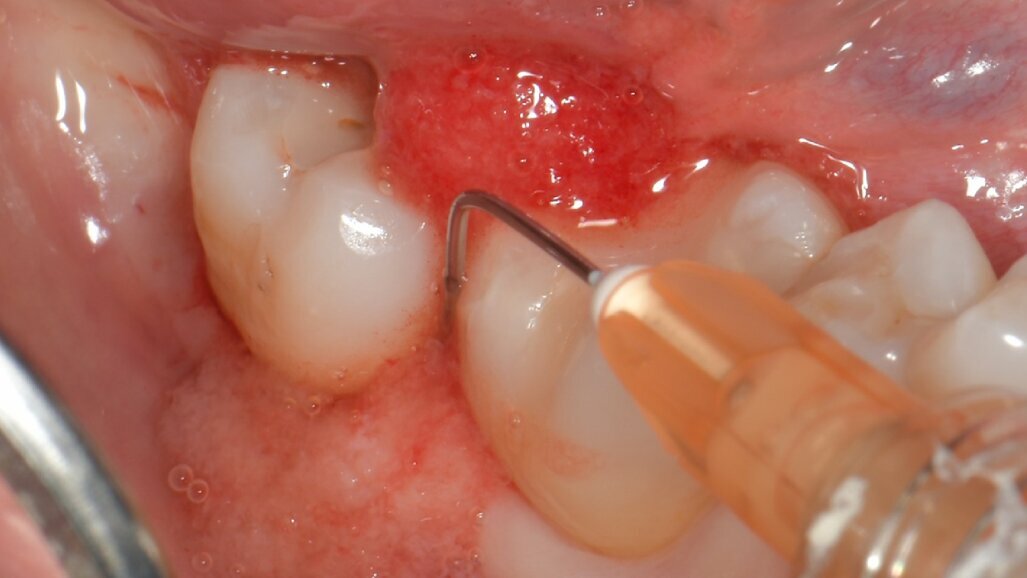

Fig. 5 - Fase di setting del prodotto H42. Il sito deve essere tenuto asciutto per 5 minuti dopo l’applicazione di H42 per favorirne l’adesione ai tessuti. Il prodotto è messo a colmare completamente la tasca, fino a uscirne.